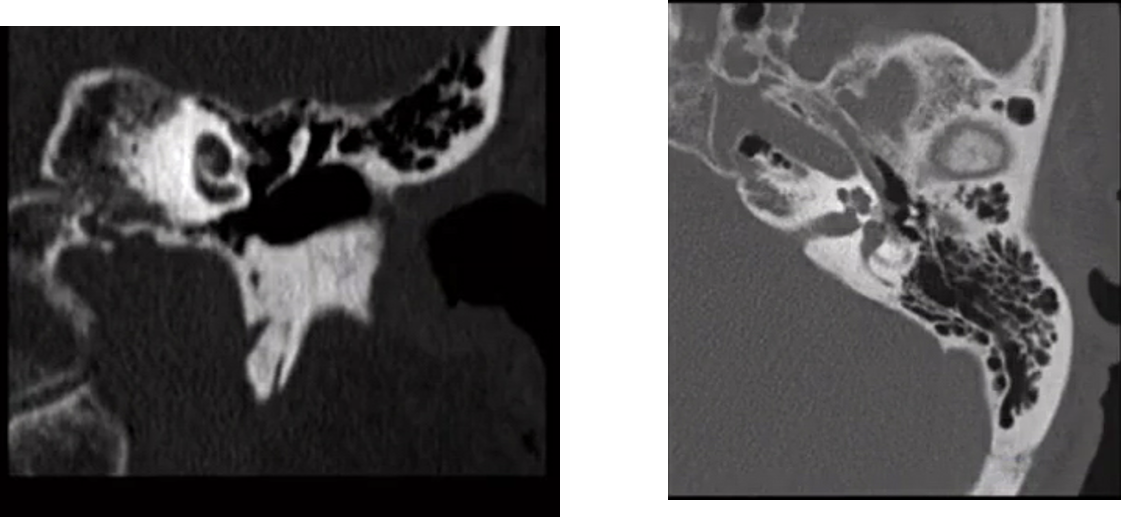

50yoM with diabetes.

Necrotizing external otitis

Classic inferior EAC osseous destruction and inflammatory tissue within the medial EAC.

Typical organism is pseudomonas aeruginosa.

95% of adults with NEO have diabetes